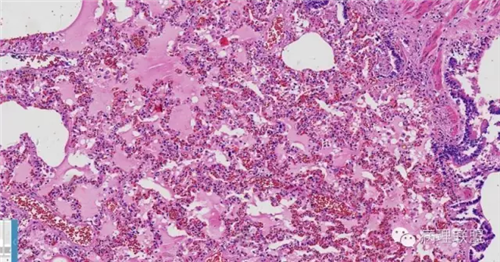

肺的

不仅仅是肺水肿